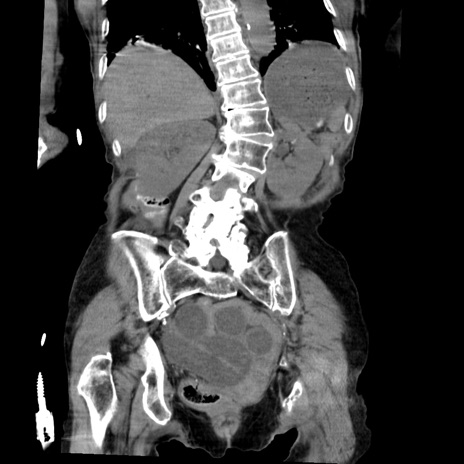

症例27(冠状断像)

【症例】80歳代女性

【主訴】嘔吐、腹痛

【現病歴】数時間前より嘔吐あり。心窩部痛出現し、徐々に右下腹痛あり。その後も数回嘔吐あり救急搬送となる。

【既往歴】左大腿骨頚部骨折手術

【身体所見】腹部は膨隆しているが軟らかく圧痛なし。腸雑音はやや亢進。

【データ】WBC 12000、CRP 19.05